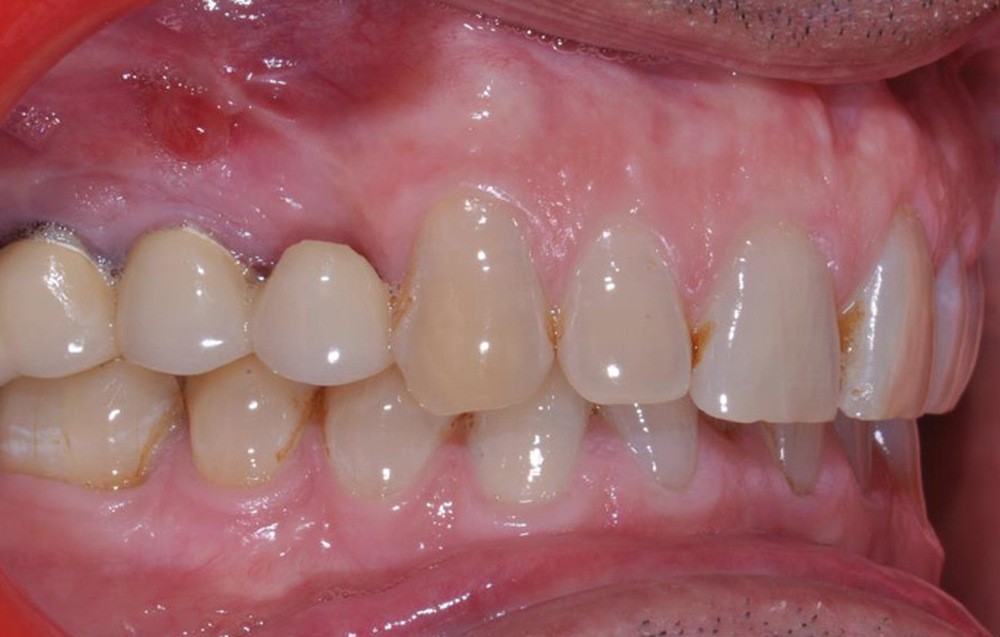

Présentation du cas clinique (fig. 1 à 3)

Le patient, âgé de 58 ans, présente un encombrement dentaire mandibulaire de 5 mm dans un contexte squelettique hypodivergent.

À la radiographie panoramique, on constate une lésion apicale sur 15 et une atteinte inter radiculaire sur 16 ainsi qu’une légère rotation de 21 sans gêne pour le patient.

Le plan de traitement établi conjointement avec son chirurgien-dentiste traitant consiste à réaliser un alignement dentaire mandibulaire et à réaliser des extractions de 16 et 15 pour un remplacement par prothèse implanto-portée.